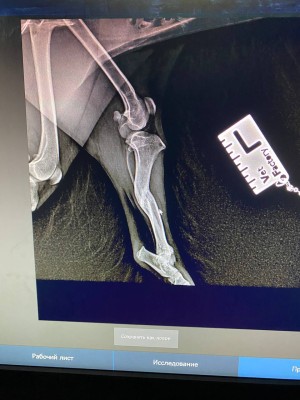

Сходили к ортопеду, у Люси перелом лапы в трех местах, уже сросшийся. Предлагают операцию в 2 этапа.

вот это перелом...она не под машину или какой транспорт попала, интересно. У нее получается в нижнем переломе верхняя часть кости срочлась с серединой нижнего обломка?

Похоже, что под машину. Когда ее нашли, видимо, свежий был перелом. Но пока волонтеры там мумили, хотя мы сразу согласились забрать, срослось все наперекосяк(Анастасия Нибелунг писал(а): ↑10 апр 2026, 20:33 вот это перелом...она не под машину или какой транспорт попала, интересно. У нее получается в нижнем переломе верхняя часть кости срочлась с серединой нижнего обломка?

Оксана ездила с Люсей ещё раз в Колпино на консультацию:

Возможно будет 3 этапа операций, поскольку у Люсьенки по КТ стало понятно , что еще повреждена голень, вывернута неестественно вправо.

Первый этап не меняется. Начинаем с таза, делают резекцию, если правильно запомнила. Реабилитация 2-4 месяца. Смотрим по итогу как встанет лапа, возможно, нам повезет и больше операций не потребуется. Стоимость первого этапа 30 тыс.

Если после первой операции и реабилитации понимаем, что лапа не встала до конца в естественное положение, следующий этап колено. Опять реабилитация, смотрим итог. И если снова лапа не выравнивается, дальше чиним голень. Но мы держим кулачки и надеемся, что обойдемся одной операцией, максимум двумя